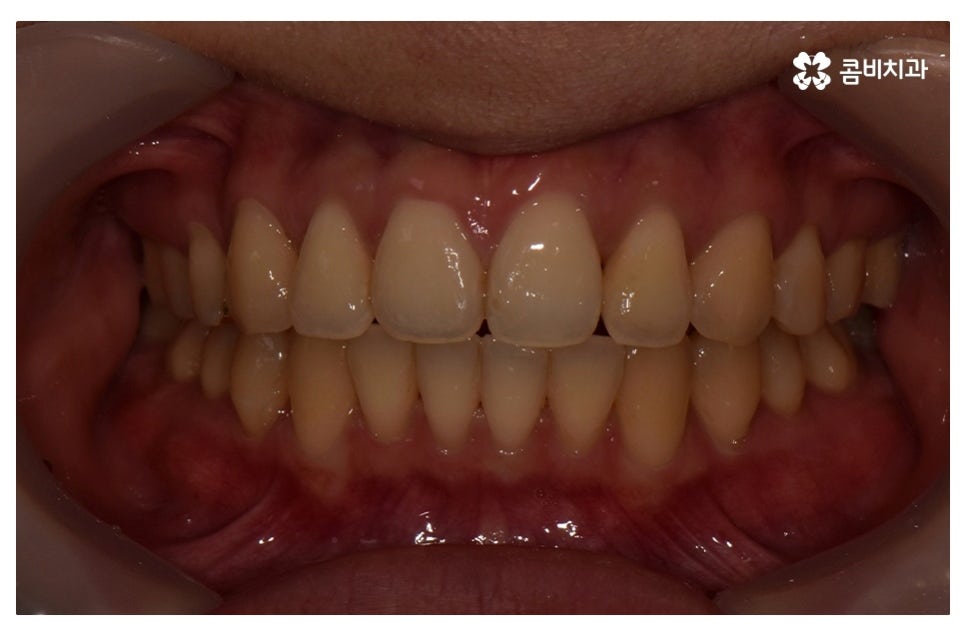

위 환자분의 경우 덧니교정에 걸린 치료 기간은 약 24개월 정도이며

성인 이후에 치료를 진행한 사례라고 볼 수 있어요.

- 개인마다 치료 기간 및 결과가 다를 수 있으므로 정확한 상담이 중요할 수 있어요 -

치아교정은 교정 결과가 우선적으로 중요하겠지만

장치를 풀어낸 이후에는 결과가 잘 유지되도록 꾸준히 잘 관리를

해야 하고 주기적으로 치과를 찾아야 하기 때문에

장기적인 관점으로 믿고 찾을 치과 선택과

담당 의사와의 소통이 중요한 치료라고 할 수 있어요.